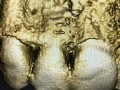

Augmentacja boczna wąskich wyrostków zębodołowych z…